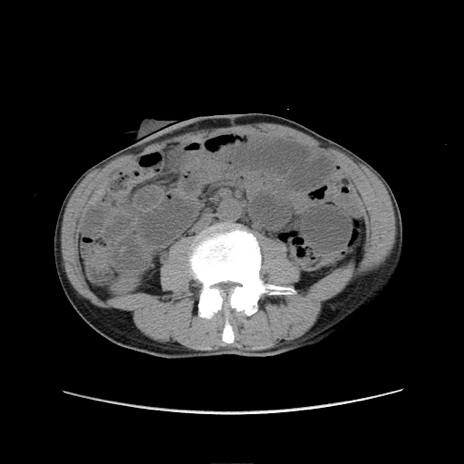

冠状断像

【症例】 60歳代男性

【主訴】 下腹部痛

【現病歴】 本日夜中より下腹部痛の症状認め、受診。

【既往歴】 膀胱癌(膀胱全摘+尿管皮膚瘻術) 、胃癌術後

【身体所見】 BT 35.3℃、PR 58/min、BP 136/98mHg、腹部平坦、軟、腸蠕動音±、ストマ留置あり、左上腹部~正中部に圧痛あり、反跳痛なし。

【データ】WBC 5100、CRP0.01